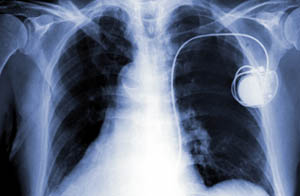

Pacemakers are small electrical devices that regulate electrical activity in the heart. Anything that produces a strong electromagnetic field can interfere with a pacemaker.